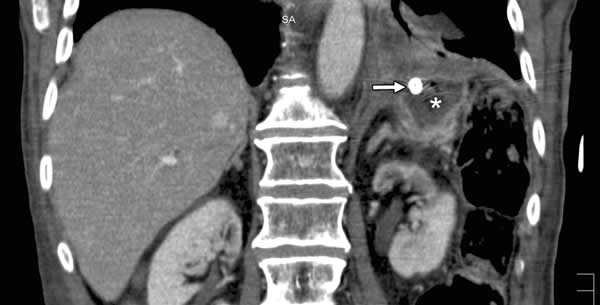

Osim anamneze i klinčkog pregleda (koji ne mora biti od velike koristi), dijagnoza se postiže RTG snimkom abdomena gdje se ispod dijafragme i iznad jetre nalazi visok stav dijafragme.